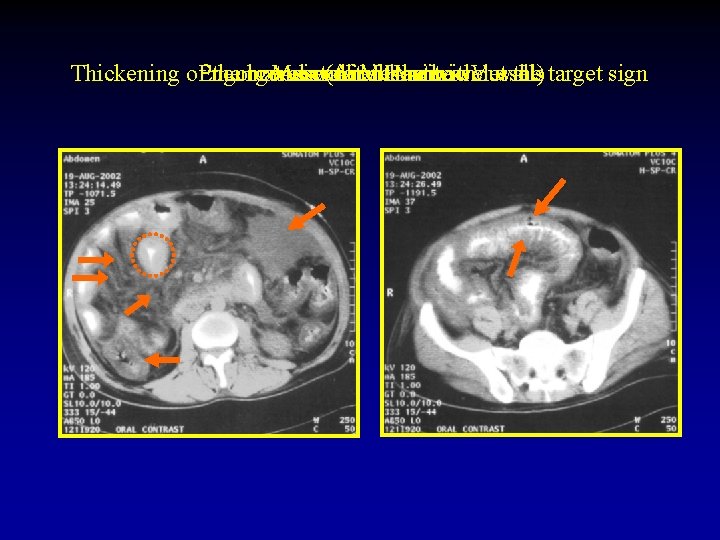

6. Are there signs of threatened bowel wall viability or not? The CT signs of threatened bowel wall viability: 1) Thickening of the bowel wall with or without the target sign. 2) Pneumatosis (Air in the bowel wall). 3) Portal venous gas. 4) Increased density of the bowel wall without intravenous contrast administration. 5) Mesenteric haziness, fluid, or hemorrhage often associated with generalized ascites. 6) On intravenous contrast enhanced CT, non enhancement, or rarely increased enhancement of the bowel.

Thickening of. Pneumatosis Engorgement the bowel Mesenteric Associated wall (Air of with Mesenteric in. Haziness Ascites the or bowel without Vessels wall) the target sign